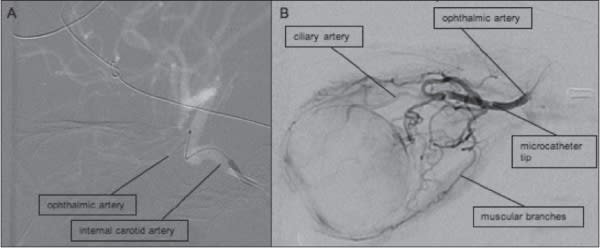

A unique method of chemotherapy delivery is the intraarterial technique (Figure 2), whereby medication is delivered directly to the affected organ by intra-arterial catheter. This concept was popularized in the 1990s and used to treat head and neck tumors, pancreatic tumors, liver tumors and other malignancies. The technique allows for concentrated, high-dose administration of chemotherapy to a focal site with limited systemic side effects. It is especially useful for small vessels such as the ophthalmic artery and was explored by Japanese researchers for use in retinoblastoma.16 Abramson et al. in 2008 published preliminary reports on nine patients treated with intra-arterial chemotherapy and demonstrated good tumor regression with minimal systemic and local toxicity.17

Figure 2. Angiography during the intra-arterial procedure demonstrating the microcatheter in the internal carotid artery (A) about to make the turn into the ophthalmic artery. Angiography done after the catheter enters the ophthalmic artery and before injection of chemotherapy shows the vasculature of the globe (B).